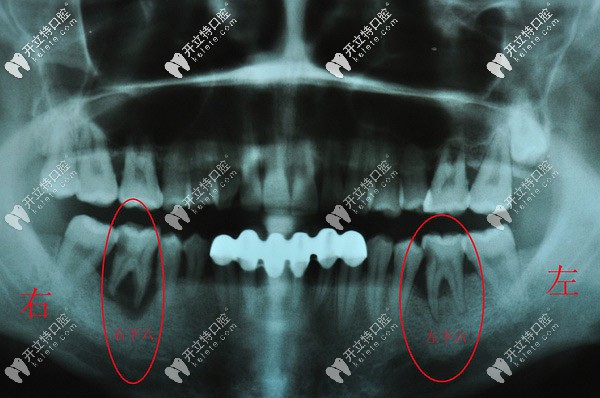

分享一則三度松動(dòng)牙齒拔除的病例,都是重度牙周炎惹的禍

拔牙牙周炎怎么治療大牙松動(dòng)發(fā)布時(shí)間: 2025-04-13

淄博高新博凡口腔日前接診了一位因重度牙周炎導(dǎo)致的三度牙齒松動(dòng)拔除病例,關(guān)于三度松動(dòng)牙是否有保留的必要本文也詳細(xì)講解,希望對(duì)大伙兒有所幫助!